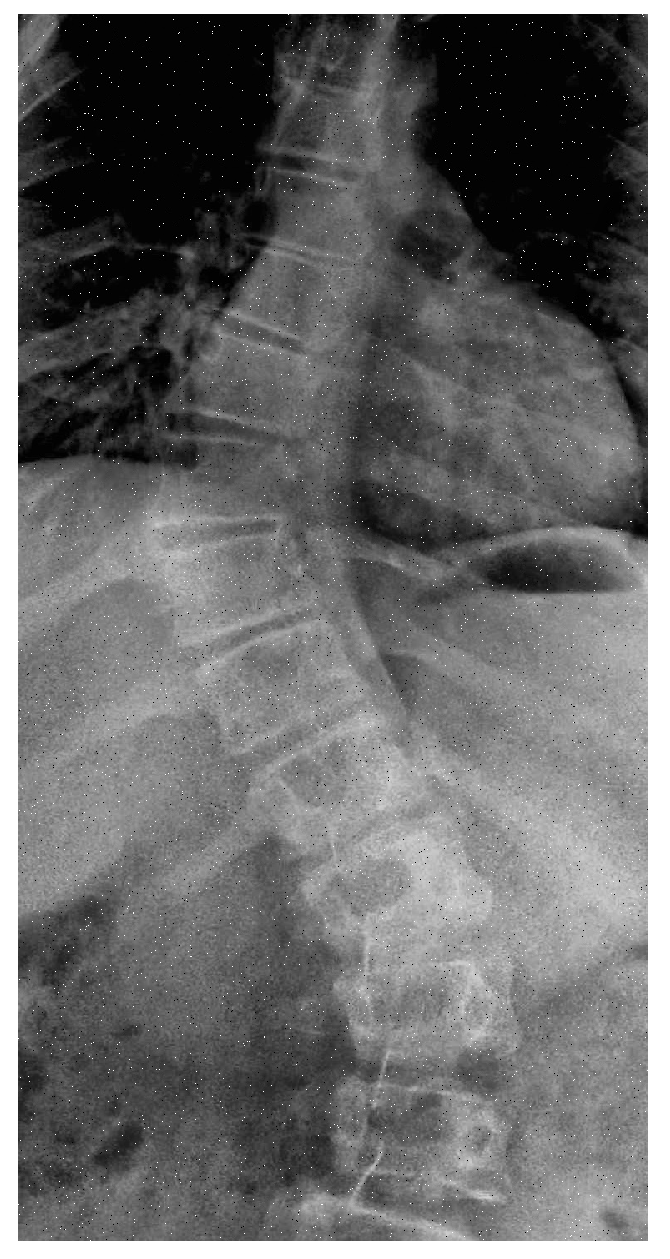

After adding noise to a chunk of dataset, Intelligent cropping is done to the next slab. Intelligent cropping means smartly determining the focal point of picture and keeping it in focus while the image is being cropped. To find the focus point, personalized code is written which crops the image from the upper portion and lower portion by keeping the spine in center. Figure 8 shows a sample of intelligent cropping by eliminating some upper and lower portion from image and making the center in focus.

The first two data augmentation techniques does not increase the sample size in real terms because both type of noise i.e: gaussian and impluse noise, is added to some existing portion of dataset and replaced with the original one. To increase the instances, images are rotated and flipped. Every image in the dataset is given a reversed and rotated rendition, n degree clockwise revolution is carried out for the image, and the same procedure is used for their relevant masks.

For the next slab of 10 percent, intelligent cropping is performed which set the upper crop limit to 0.15 ratio and the lower limit to 0.25 of the original image’s height and width, making the spine portion in center, presented in Figure 16.

Figure 8. Intelligently Cropped Image.

Figure 16. Intelligently Cropped Image.